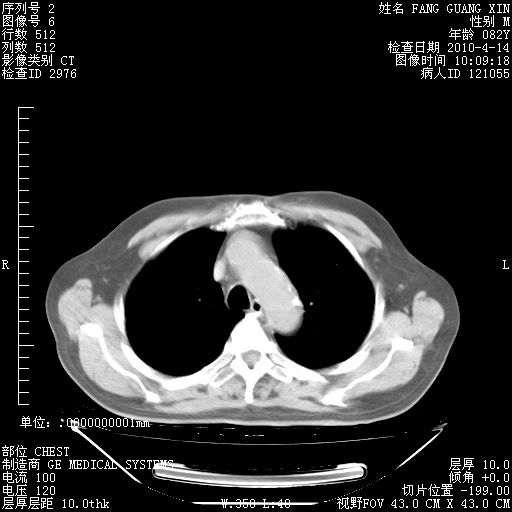

4月14日肺部CT